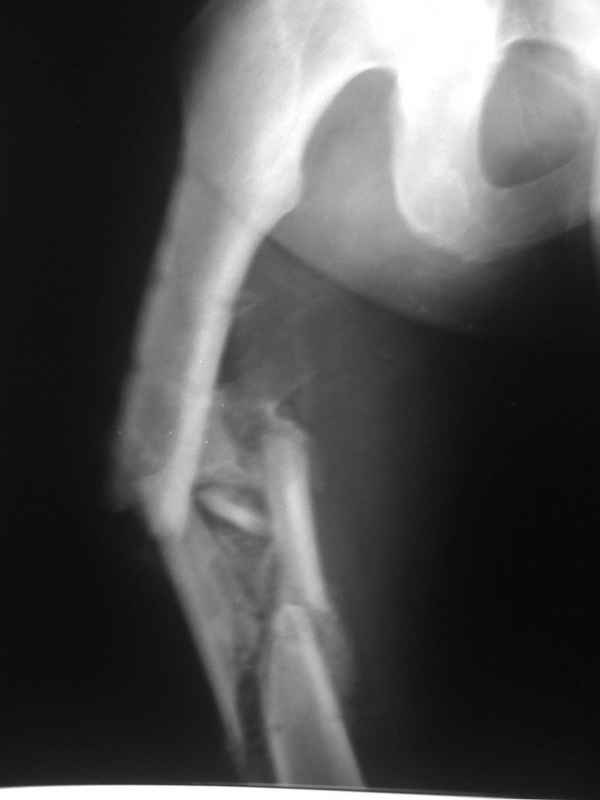

Re: Неправильно срастающийся оскольчатый перелом бедра

Конечно, снимки для планирования надо нормальные, не такой огрызок.

Можно закрыто мобилизовать отломки, наложить дистракционный аппарат, восстановить ось и длину, да и заштифтовать, на всякий случай с антибиотиковым цементным покрытием.

Спасибо за снимки. Предложения по тактике прежние.

Вы думаете, что в данной ситуации возможна закрытая мобилизация?

Попробовать-то можно. И просто руками "об колено", а то и наложить аппарат, приложить флексионные и ротационые усилия прямо за разъединенные секции.

Если уж никак, то сделать чрескожную остеотомию.

Но если картинки недавние, IMHO должно получиться закрыто разобщить.